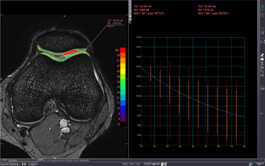

MR TX MAPPING

Using MR data with different TE and spin lock times, this protocol measures T2, T2*, or T1rho values of the specified ROI and shows color maps.